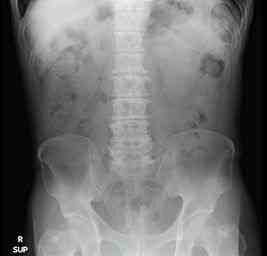

上は正常の腹部レントゲン写真ですが、白くはっきり写っているのは腰椎や骨盤、大腿骨といった骨で、黒く抜けているのは、腸管のガス像です。その他、肝臓、脾臓、腎臓、膀胱といった内部臓器も淡く写っていますが、なかなか分かりにくいですよね。

レントゲンというのは、基本的に骨・水・脂肪・空気・石灰化・金属(治療した人工物)といった大きく6種類のものを比較し、これらを淡い影の変化で見分けているのです。レントゲンで便が多いですねなどと言われたことある方がいるかもしれませんが、実際には便そのものが見えているわけではありません。あくまでも脂肪や水成分の組織に囲まれて明瞭となった腸管ガス像をみて、その存在を推測しているだけなのです。